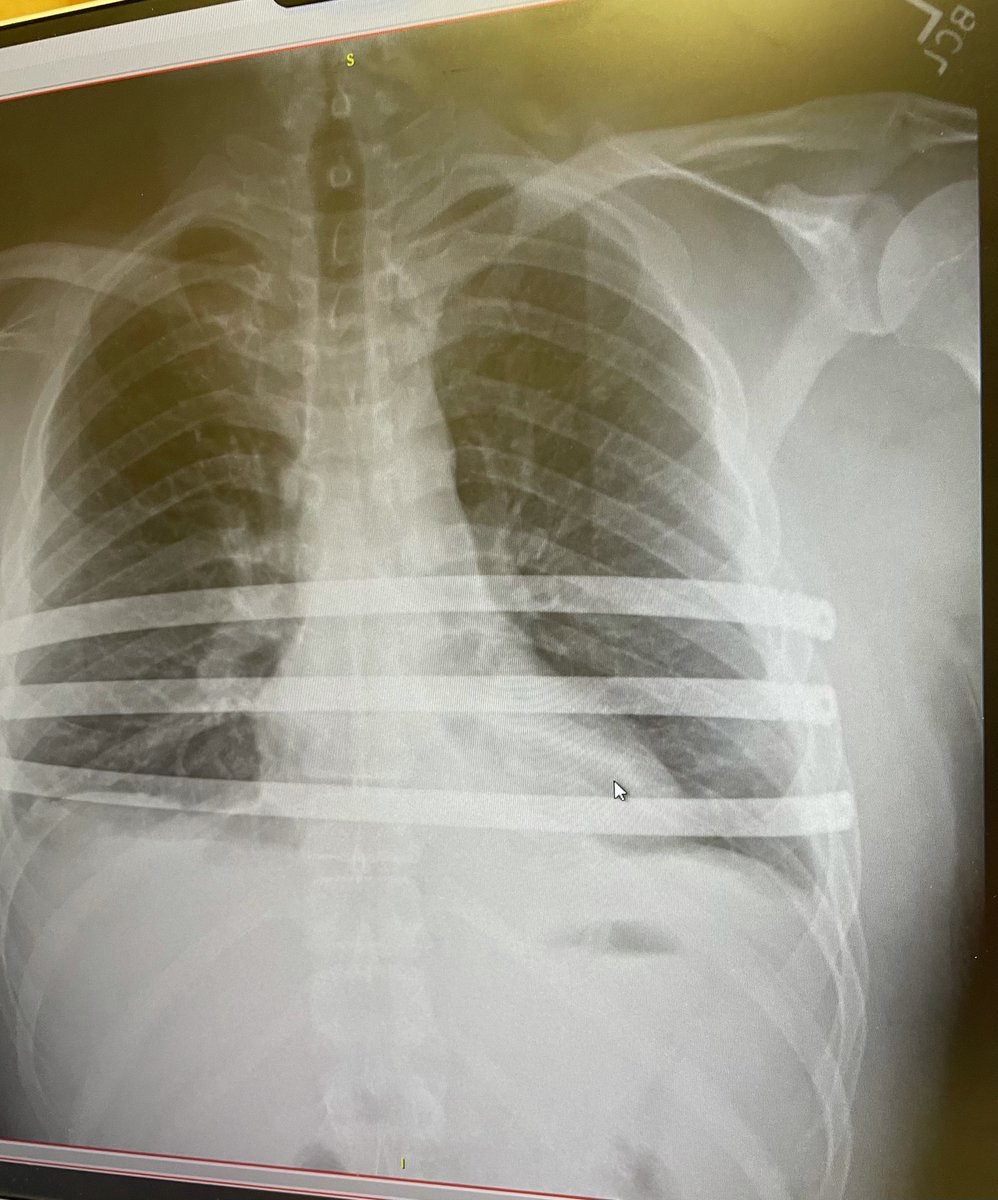

Steven Crowder Twitter - Hilary Agro On Twitter He Deleted It So I Just Want To Make Sure Everyone Sees That Steven Crowder Has Managed To Hit A New Low - I'm actually looking forward to it.. Steven crowder twitter content warning: The 2nd amendment was designed to allow citizens to protect themselves from an internal or external threat on their home, property or against a tyrannical government. Jul 28, 2021 · news steven crowder conservative political commentator steven crowder was trending on twitter on wednesday after he shared a photo of himself in hospital, days after revealing he had a collapsed lung. Ever actually get so close that you can physically feel death? Last friday, conservative commentator steven crowder announced that he was.

May 17, 2021 · steven crowder ‏ verified account @scrowder 3h 3 hours ago follow follow @ scrowder following following @ scrowder unfollow unfollow @ scrowder blocked blocked @ scrowder unblock unblock @ scrowder pending pending follow request from @ scrowder cancel cancel your follow request to @ scrowder Ever actually get so close that you can physically feel death? Jul 28, 2021 · news steven crowder conservative political commentator steven crowder was trending on twitter on wednesday after he shared a photo of himself in hospital, days after revealing he had a collapsed lung. The good news is, it's fixable and these things … Jul 28, 2021 · source:

Ever actually get so close that you can physically feel death? The good news is, it's fixable and these things happen. The good news is, it's fixable and these things … He hosts louder with crowder, a daily political podcast and youtube channel. Many of the tweets embedded in this article contain explicit language. I'm actually looking forward to it. The update, sent out via his personal twitter account, was met with almost instant trolling as many users used it as an opportunity to target crowder. Jul 28, 2021 · news steven crowder conservative political commentator steven crowder was trending on twitter on wednesday after he shared a photo of himself in hospital, days after revealing he had a collapsed lung.

Jul 29, 2021 · louder with crowder host steven crowder posted a photo of himself on tuesday and indicated that he had recently come close to death.last night took a turn for the worse.

The good news is, it's fixable and these things happen. Steven crowder twitter content warning: I'll be back before you know it. Last friday, conservative commentator steven crowder announced that he was. I'm actually looking forward to it. Jul 28, 2021 · source: He is particularly notable for a recurring. The 2nd amendment was designed to allow citizens to protect themselves from an internal or external threat on their home, property or against a tyrannical government. We would like to show you a description here but the site won't allow us. Jul 28, 2021 · news steven crowder conservative political commentator steven crowder was trending on twitter on wednesday after he shared a photo of himself in hospital, days after revealing he had a collapsed lung. Last night took a turn for the worse. May 17, 2021 · steven crowder ‏ verified account @scrowder 3h 3 hours ago follow follow @ scrowder following following @ scrowder unfollow unfollow @ scrowder blocked blocked @ scrowder unblock unblock @ scrowder pending pending follow request from @ scrowder cancel cancel your follow request to @ scrowder On july 27, crowder tweeted he could physically feel death as his situation took a turn for the worse.

Last night took a turn for the worse. We would like to show you a description here but the site won't allow us. On july 27, crowder tweeted he could physically feel death as his situation took a turn for the worse. Jul 28, 2021 · conservative commentator steven crowder, 34, took to instagram and twitter to share a photo of himself as he recovers from an operation. Last friday, conservative commentator steven crowder announced that he was. Steven crowder twitter content warning: Ever actually get so close that you can physically feel death? Jul 29, 2021 · louder with crowder host steven crowder posted a photo of himself on tuesday and indicated that he had recently come close to death.last night took a turn for the worse.